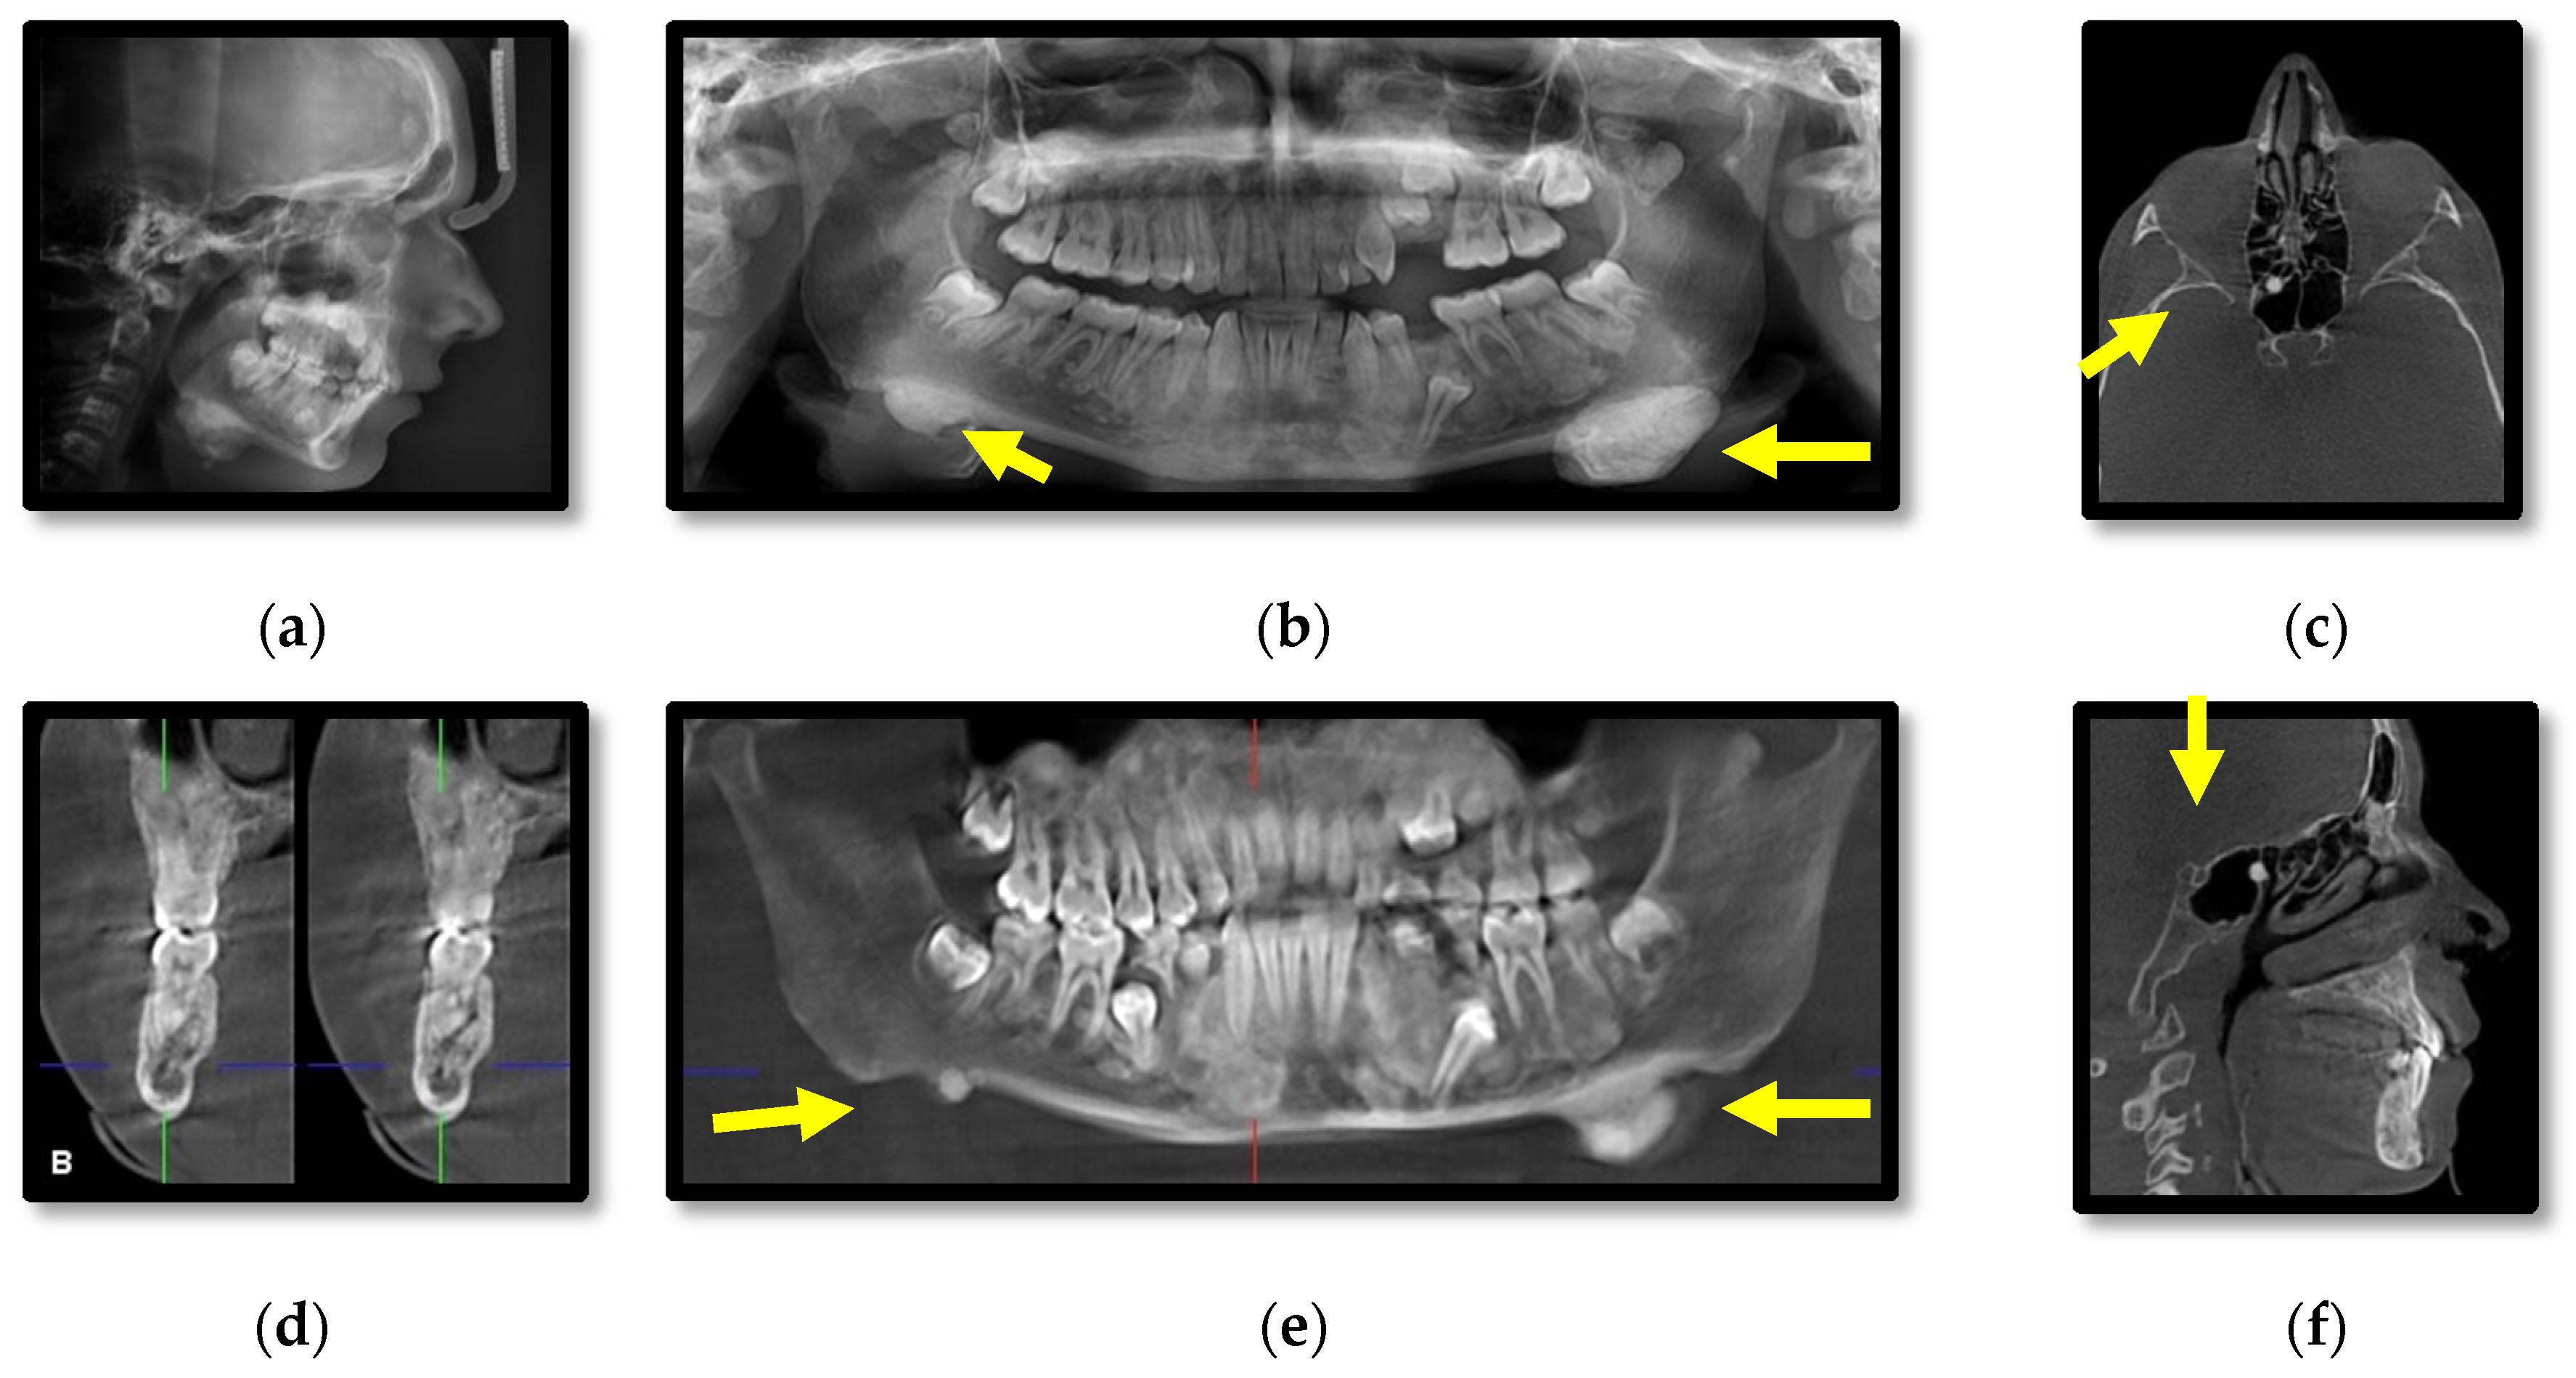

3.1. Radiographic Assessment

4.2. Osteomas

- Cankaya, A.B.; Erdem, M.A.; Isler, S.C.; Cifter, M.; Olgac, V.; Kasapoglu, C.; Oral, C.K. Oral and maxillofacial considerations in Gardner’s syndrome. Int. J. Med. Sci. 2012, 9, 137. [Google Scholar] [CrossRef] [PubMed]

- Almeida, F.T.; Pachêco-Pereira, C.; Porporatti, A.L.; Flores-Mir, C.; Leite, A.F.; De Luca Canto, G.; Guerra, E.N.S. Oral manifestations in patients with familial adenomatous polyposis: A systematic review and meta-analysis. J. Gastroenterol. Hepatol. 2016, 31, 527–540. [Google Scholar] [CrossRef] [PubMed]

- Wijn, M.A.; Keller, J.J.; Giardiello, F.M.; Brand, H.S. Oral and maxillofacial manifestations of familial adenomatous polyposis. Oral Dis. 2007, 13, 360–365. [Google Scholar] [CrossRef] [PubMed]

- Ida, M.; Nakamura, T.; Utsunomiya, J. Osteomatous changes and tooth abnormalities found in the jaws of patients with adenomatosis coli. Oral Surg. Oral Med. Oral Pathol. 1981, 52, 2–11. [Google Scholar] [CrossRef]

- Oku, T.; Takayama, T.; Sato, Y.; Sato, Y.; Takada, K.; Hayashi, T.; Takahashi, M.; Kuroda, M.; Kato, J.; Niitsu, Y. A case of Gardner syndrome with a mutation at codon 1556 of APC: A suggested case of genotype–phenotype correlation in dental abnormality. Eur. J. Gastroenterol. Hepatol. 2004, 16, 101–105. [Google Scholar] [CrossRef]